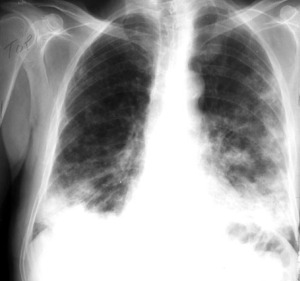

Dois estudos publicados nesta quarta-feira, 2 de setembro, confirmam a utilidade desses fármacos na terapia de casos graves da Covid-19, também marcados por uma reação inflamatória exagerada.

Fonte: Corticoides diminuem mortalidade em casos graves de Covid-19, confirmam estudos